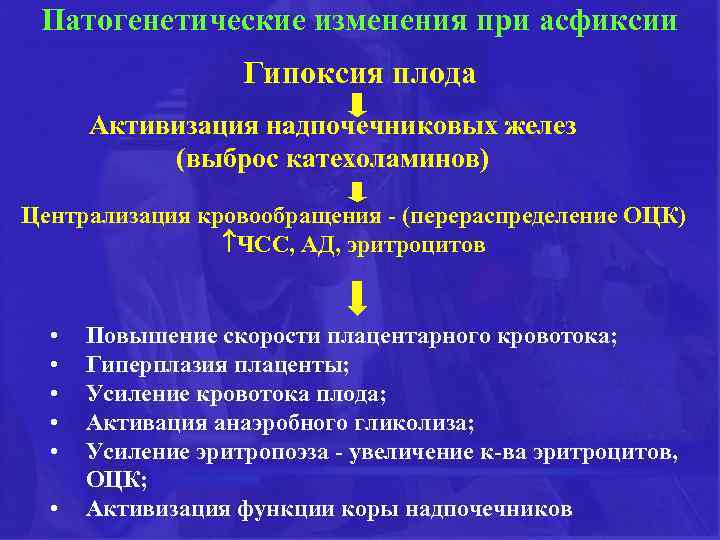

Патогенетические изменения при асфиксии Гипоксия плода Активизация надпочечниковых желез (выброс катехоламинов) Централизация кровообращения - (перераспределение ОЦК) ЧСС, АД, эритроцитов • • • Повышение скорости плацентарного кровотока; Гиперплазия плаценты; Усиление кровотока плода; Активация анаэробного гликолиза; Усиление эритропоэза - увеличение к-ва эритроцитов, ОЦК; Активизация функции коры надпочечников

Патогенетические изменения при асфиксии Гипоксия плода Активизация надпочечниковых желез (выброс катехоламинов) Централизация кровообращения - (перераспределение ОЦК) ЧСС, АД, эритроцитов • • • Повышение скорости плацентарного кровотока; Гиперплазия плаценты; Усиление кровотока плода; Активация анаэробного гликолиза; Усиление эритропоэза - увеличение к-ва эритроцитов, ОЦК; Активизация функции коры надпочечников